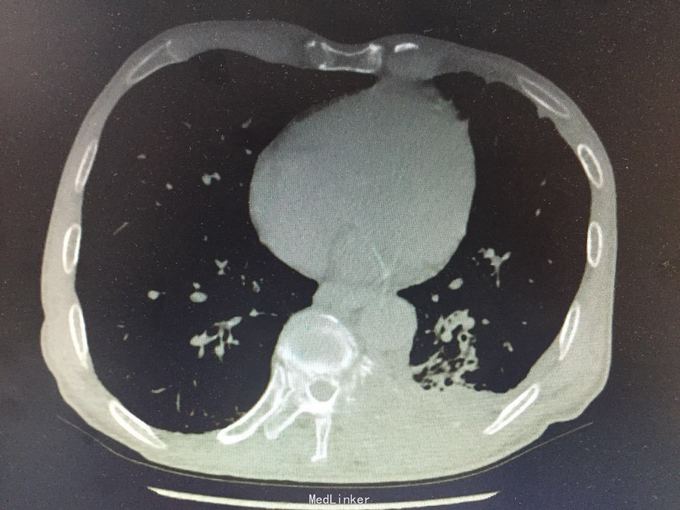

MRI示:肋骨,胸椎多发骨转移 CT示:胃Ca术后:腹膜后淋巴结转移,左侧胸膜多发转移,左侧后壁转移并T10锥体及左侧横突,第10.11后肋转移骨质破坏,骨质疏松并T12及L2压缩骨折 核医学ECT示:多发骨转移